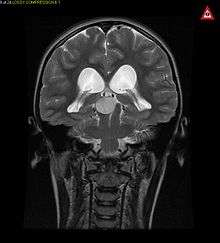

Pilocytic astrocytomas are often cystic, and, if solid, tend to be well-circumscribed. It is characteristically easily seen on CT scans and MRI.

Usually—depending on the interview of the patient and after a clinical exam which includes a neurological exam, and an ophthalmological exam—a CT scan and or MRI scan will be performed. A special dye may be injected into a vein before these scans to provide contrast and make tumors easier to identify. The neoplasm will be clearly visible.

Visual aspect

Macroscopically, an astrocytoma is a mass that looks well-circumscribed and has a large cyst. The neoplasm may also be solid.